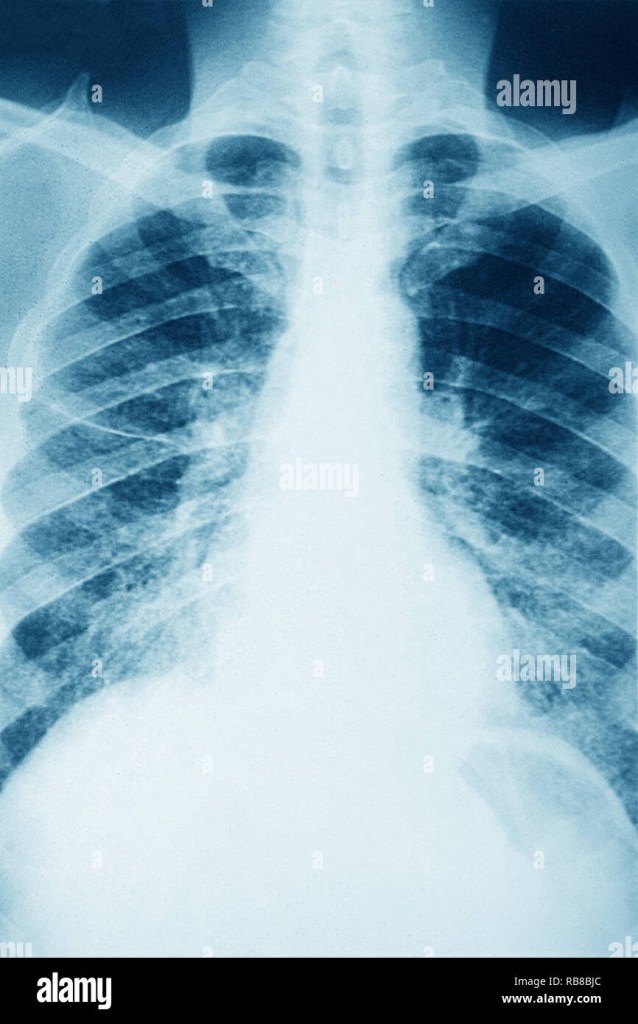

Sarcoidosis occurs in the lungs and is classified into what is the ‘Scadding Stages’ this is based on the chest X-ray findings. From Stage 0 to Stage 4. In stage 0, the X-rays do not show sarcoidosis in the lymph nodes nor the lungs. Stage 1 has lymph nodes at the centre of the chest due to the granulomas and it usually resolves on its own; Stage 2, enlargement of the lymph nodes and formation of granulomas in the chest x-ray; Stage 3, granulomas are present in just the lungs; Stage 4; permanent scarring of the tissue exhibiting pulmonary fibrosis. He was administered steroids as treatment.